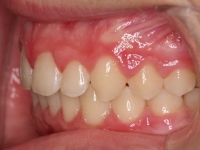

El paciente A.J. de 11 años, acude a nuestra consulta con apiñamiento maxilar importante. El canino lateral (12) está en mordida cruzada. Presenta una Clase II molar y canina, y la línea media está desviada. Se realizó un tratamiento con brackets autoligables metálicos de smartclip 022. La duración del tratamiento fue de 22 meses.

El paciente actualmente ha terminado el tratamiento con brackets y lleva una contención fija de 2-2 en maxilar y 3-3 en mandibular; para complementar también lleva una férula ESSIX durante la noche.

INICIO FINAL